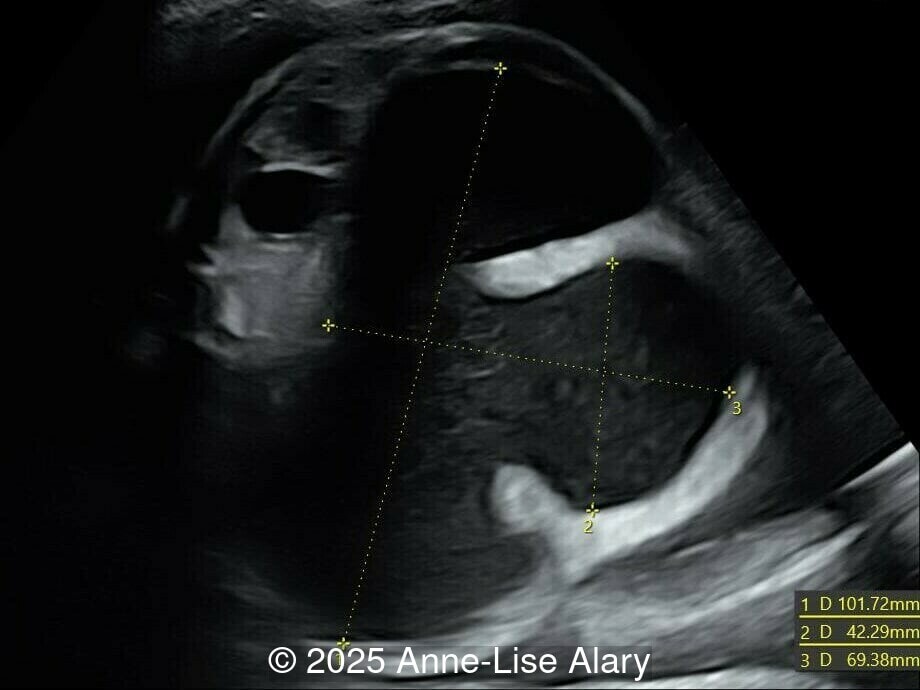

Our prenatal ultrasound revealed a male fetus with megabladder, dilation of both ureter and kidneys, and thinned kidney parenchyma consistent with Lower Urinary Tract Obstruction (LUTO). Additional findings suspected on ultrasound and confirmed on computed tomography included:

The diagnosis of PBS is often made in the second trimester of pregnancy, although it has been described as early as 11 weeks of gestation [20]. The most frequent ultrasound findings are a large, thin-walled bladder accompanied by bilateral hydroureter/hydronephrosis, dysplastic kidneys with echogenic renal parenchyma and renal cortical cysts, and abdominal wall laxity which is better viewed after bladder decompression [21]. Cryptorchidism can be detected prenatally by 28 to 30 weeks gestation when the testes descend into scrotum. There may be a patent urachus, visible as a cystic connection between bladder and umbilicus. Oligohydramnios is a frequent finding, which makes it difficult to visualize the associated anomalies.